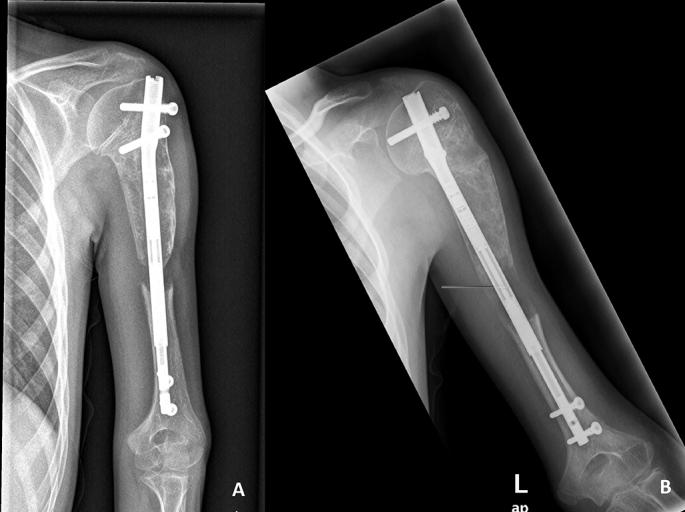

We report the treatment process of a pediatric patient with deformity and shortening in the arm after a recurrent aggressive aneurysmal bone cyst (ABC) in the proximal humerus. The patient was treated with curettage of the lesion and lengthening on an intramedullary nail following an osteotomy just distal to the ABC. The period of lengthening was approximately 50 days. At the end of the treatment the lengthening goal was achieved without any neurovascular complication. There was a minimal loss in shoulder hyperabduction due to the deformity of the humeral head.

我们报告了一名肱骨近端复发性侵袭性骨囊肿(ABC)后出现手臂畸形和缩短的儿科患者的治疗过程。患者接受了病变刮除术,并在ABC远端进行截骨后,使用髓内钉延长。延长时间约为50天。治疗结束时,达到了延长目标,且未出现任何神经血管并发症。由于肱骨头畸形,肩关节外展功能仅有轻微丧失。